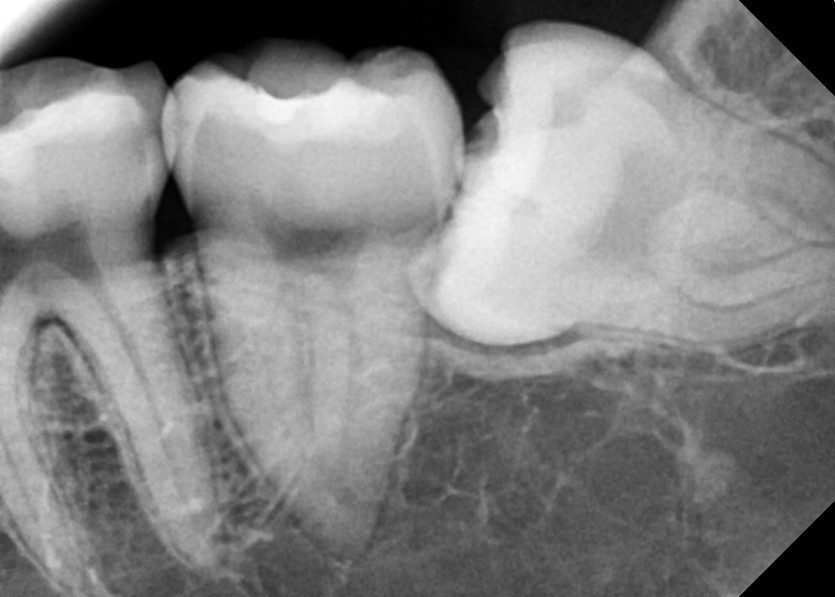

#38 사랑니 발치

구강 외과 전문의가 당일 발치했습니다.